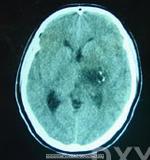

腦CT酒精中毒性神經疾病的中樞神經抑制症狀,應注意與引起昏迷的疾病相鑑別,如鎮靜催眠藥中毒、一氧化碳中毒腦卒中、顱腦外傷等戒斷綜合徵的精神症狀和癲癇發作,應與精神病、癲癇、窒息性氣體中毒低血糖征等相鑑別慢性酒精中毒的智慧型障礙和人格改變,應與其他原因引起的痴呆鑑別。

其它輔助檢查:1.心電圖、腦電圖、腦CT或MRI檢查,有鑑別診斷及中毒程度評估意義;2.肌電圖和神經電生理檢查有鑑別診斷意義。